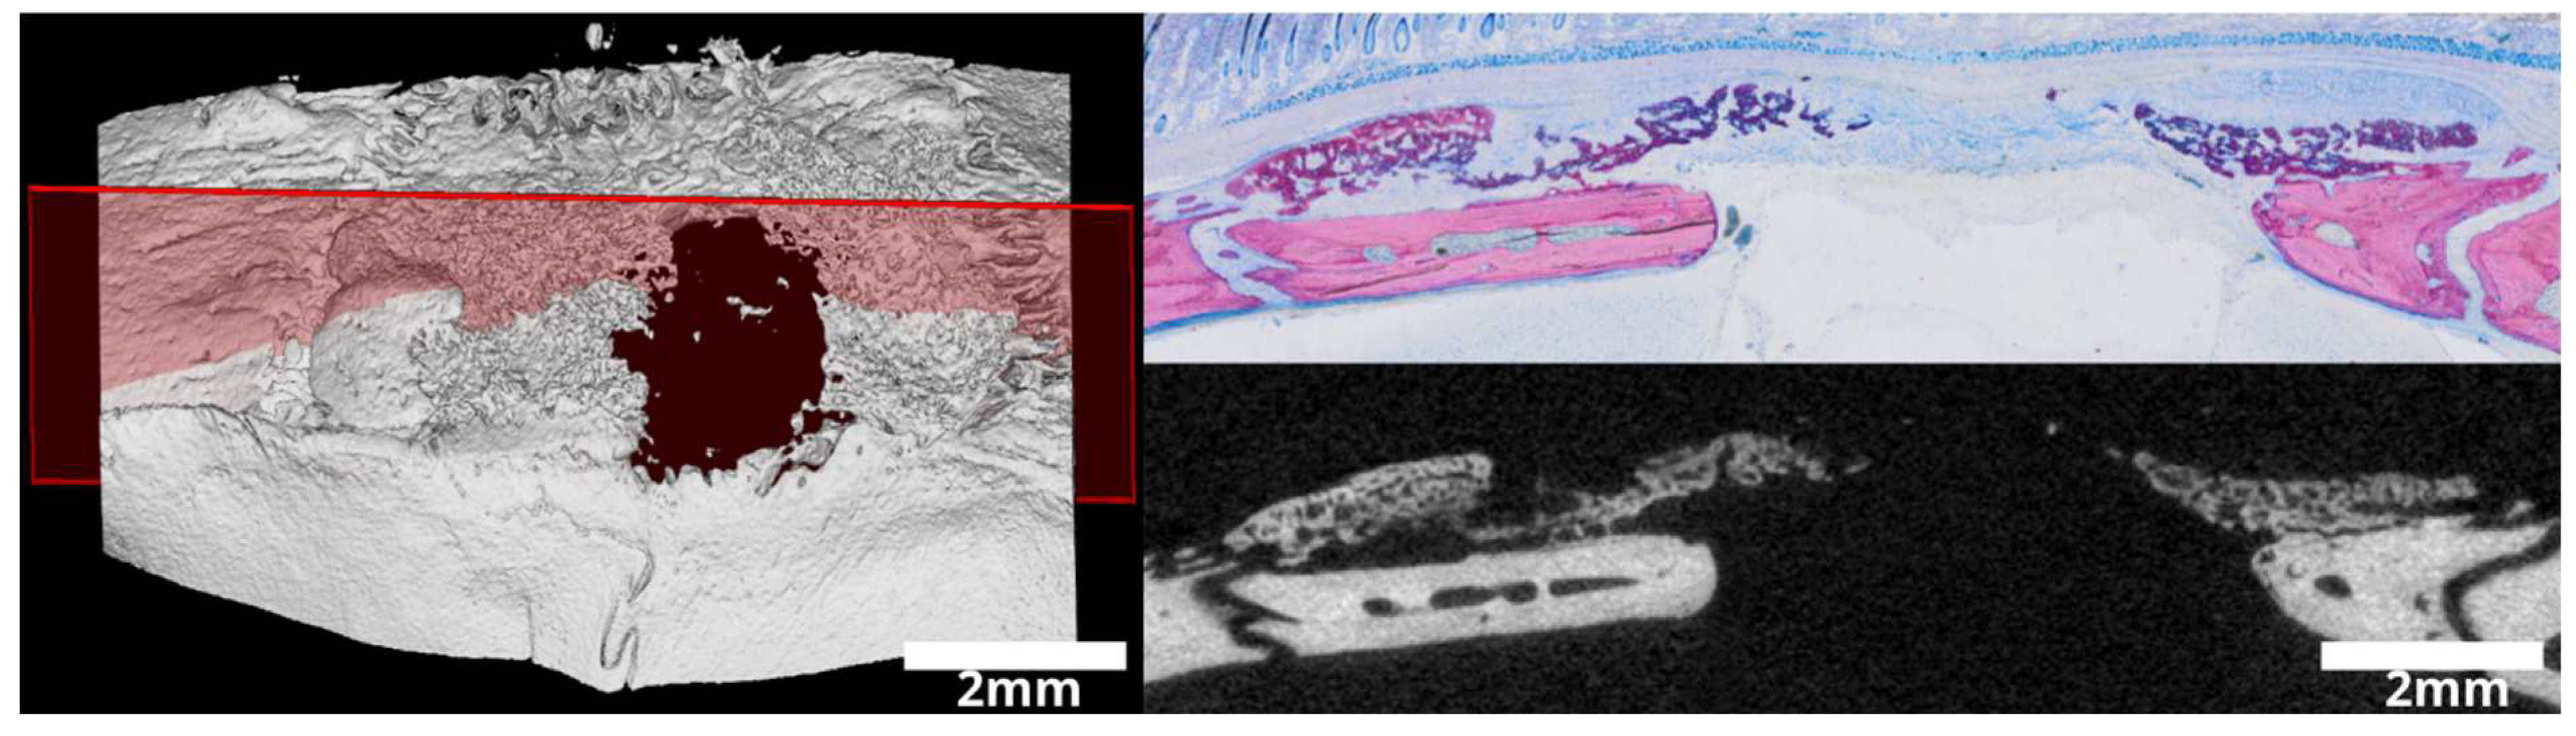

3.1. Intact and Minced Collagen Membranes: µCT Analysis